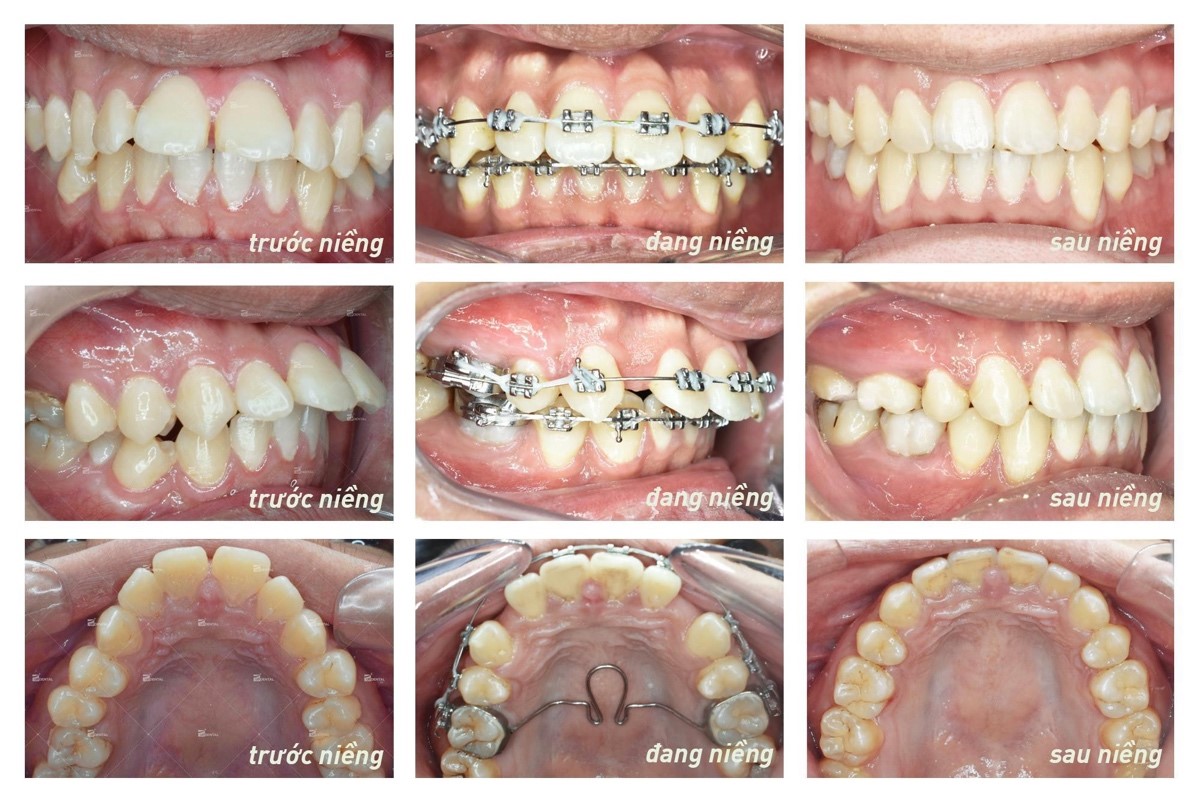

6. Tháo mắc cài và mang máng duy trì

Sau khi răng đã vào vị trí thì nha sĩ sẽ tiến hành tháo mắc cài ra và cho bệnh nhân đeo mang duy trì. Thời gian niềng sẽ giao động 1 năm rưỡi đến 2 năm rưỡi tùy vào tình trạng của bệnh nhân. Sau khi kết thúc quá trình niềng răng bệnh nhân sẽ phải mang máng duy trì trong một thời gian để răng cứng cáp hơn, tránh bị chạy về vị trí cũ.